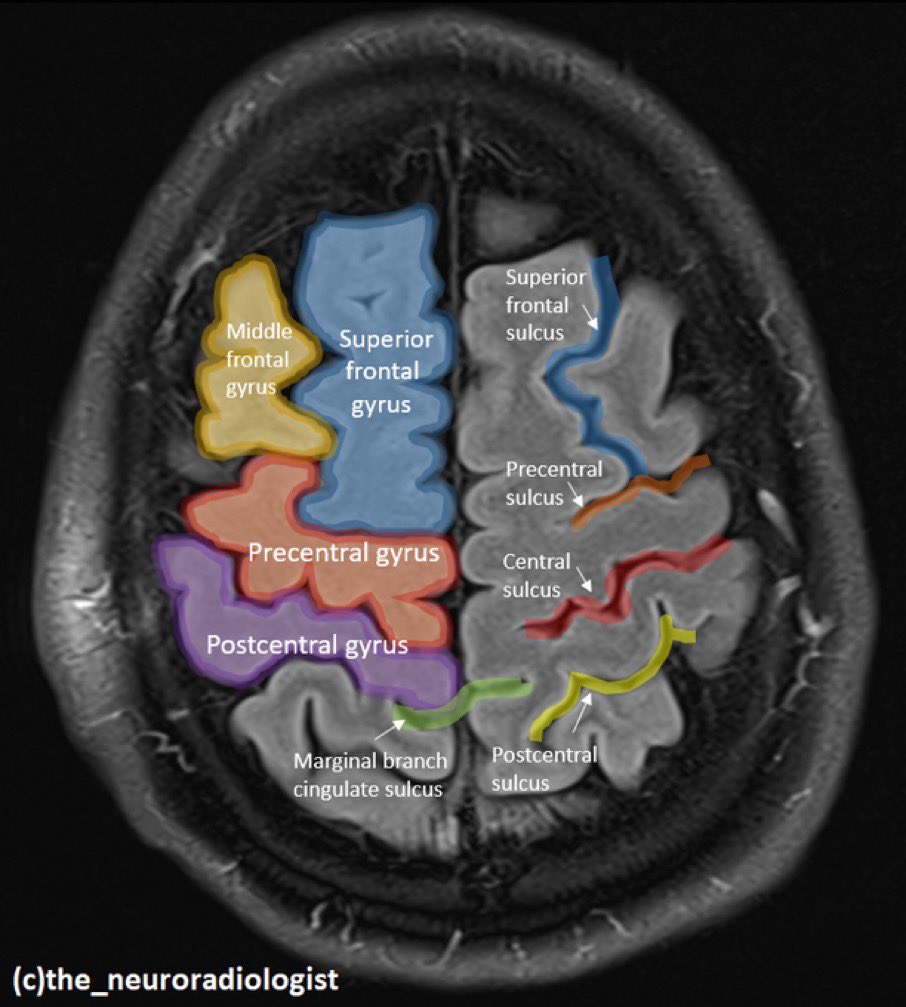

Both ChatGPT (5.3 as well as 5.0) and LeChat happily started to reason their way through the answer stating, B: Postcentral gyrus. Now, you might say, that this random image is somewhat similar to a postcentral gyrus nucleus, and that is a fair challenge. Doing Duckduckgo or Google searches bring up plenty of images. One good repesentation is as below: